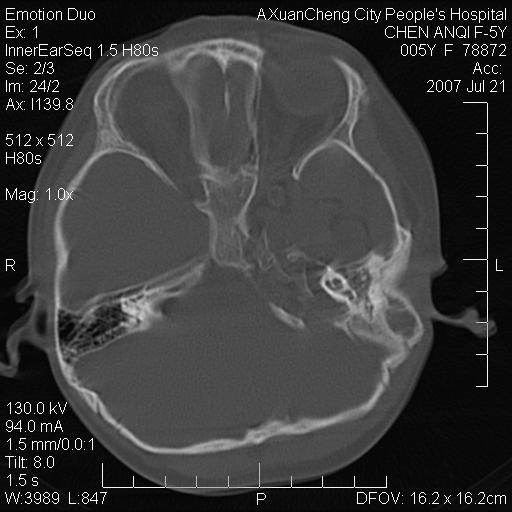

标题: PED0273:5岁,左耳流脓痛疼一周,颅底骨质破坏 [打印本页]

标题: PED0273:5岁,左耳流脓痛疼一周,颅底骨质破坏

患儿5岁,左耳流脓痛疼一周,左外耳道肉芽组织填塞 软组织窗显示病灶内结节状低密度影为气体密度

左侧中耳炎并胆脂瘤,左颞骨岩部骨质破坏并颅内感染积气。